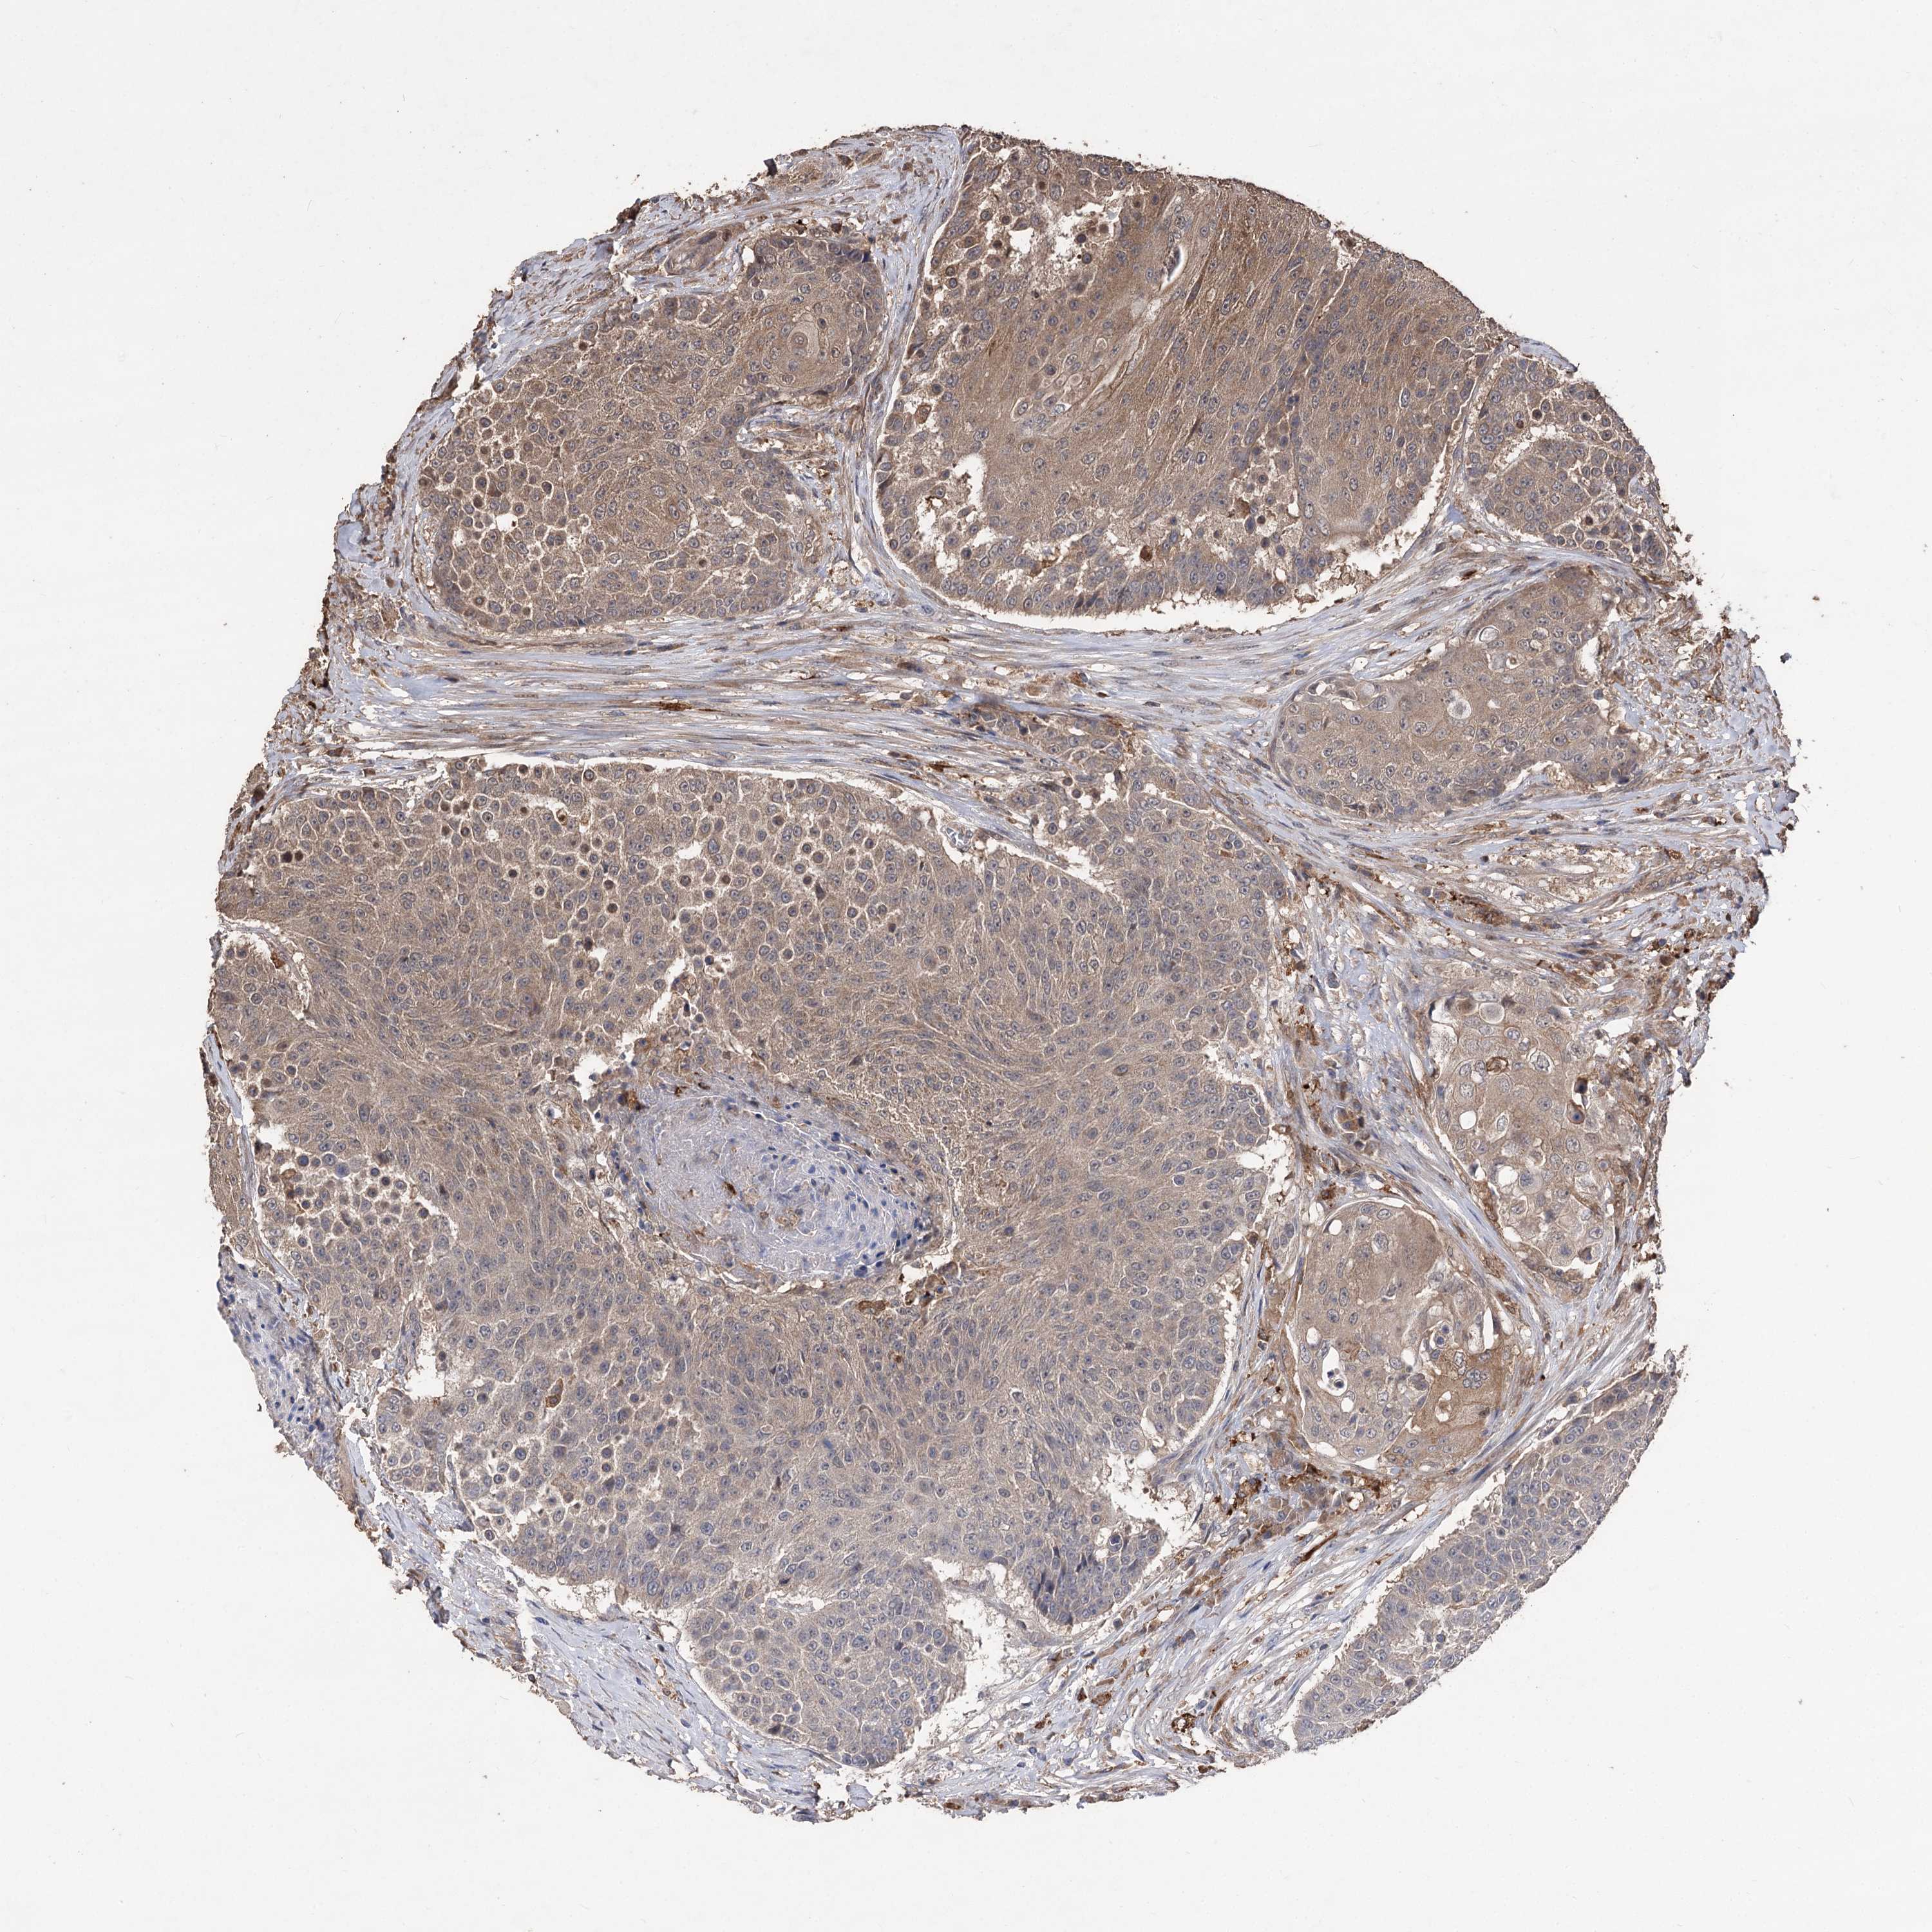

UROTHELIAL CANCER - Protein expressioni

A mouse-over function shows sample information and annotation data. Click on an image to view it in a full screen mode. Samples can be filtered based on level of antibody staining by selecting one or several of the following categories: high, medium, low and not detected. The assay and annotation is described here.

Note that samples used for immunohistochemistry by the Human Protein Atlas do not correspond to samples in the TCGA dataset.

Antibody stainingi

Antibody staining in the annotated cell types in the current human tissue is reported as not detected, low, medium, or high, based on conventional immunohistochemistry profiling in selected tissues. This score is based on the combination of the staining intensity and fraction of stained cells.

Each image is clickable and will lead to virtual microscopy that enables deeper exploration of all samples and also displays staining intensity scores, fraction scores and subcellular localization as well as patient and tissue information for each sample.

Antibody HPA038469

Antibody CAB022664

Antibody CAB034035

Staining

High

Medium

Low

Not detected

Intensity

Strong

Moderate

Weak

Negative

Quantity

>75%

75%-25%

<25%

None

Location

Nuclear

Cytoplasmic/membranous

Cytoplasmic/membranous,nuclear

Urothelial carcinoma, High grade

Urothelial carcinoma, Low grade